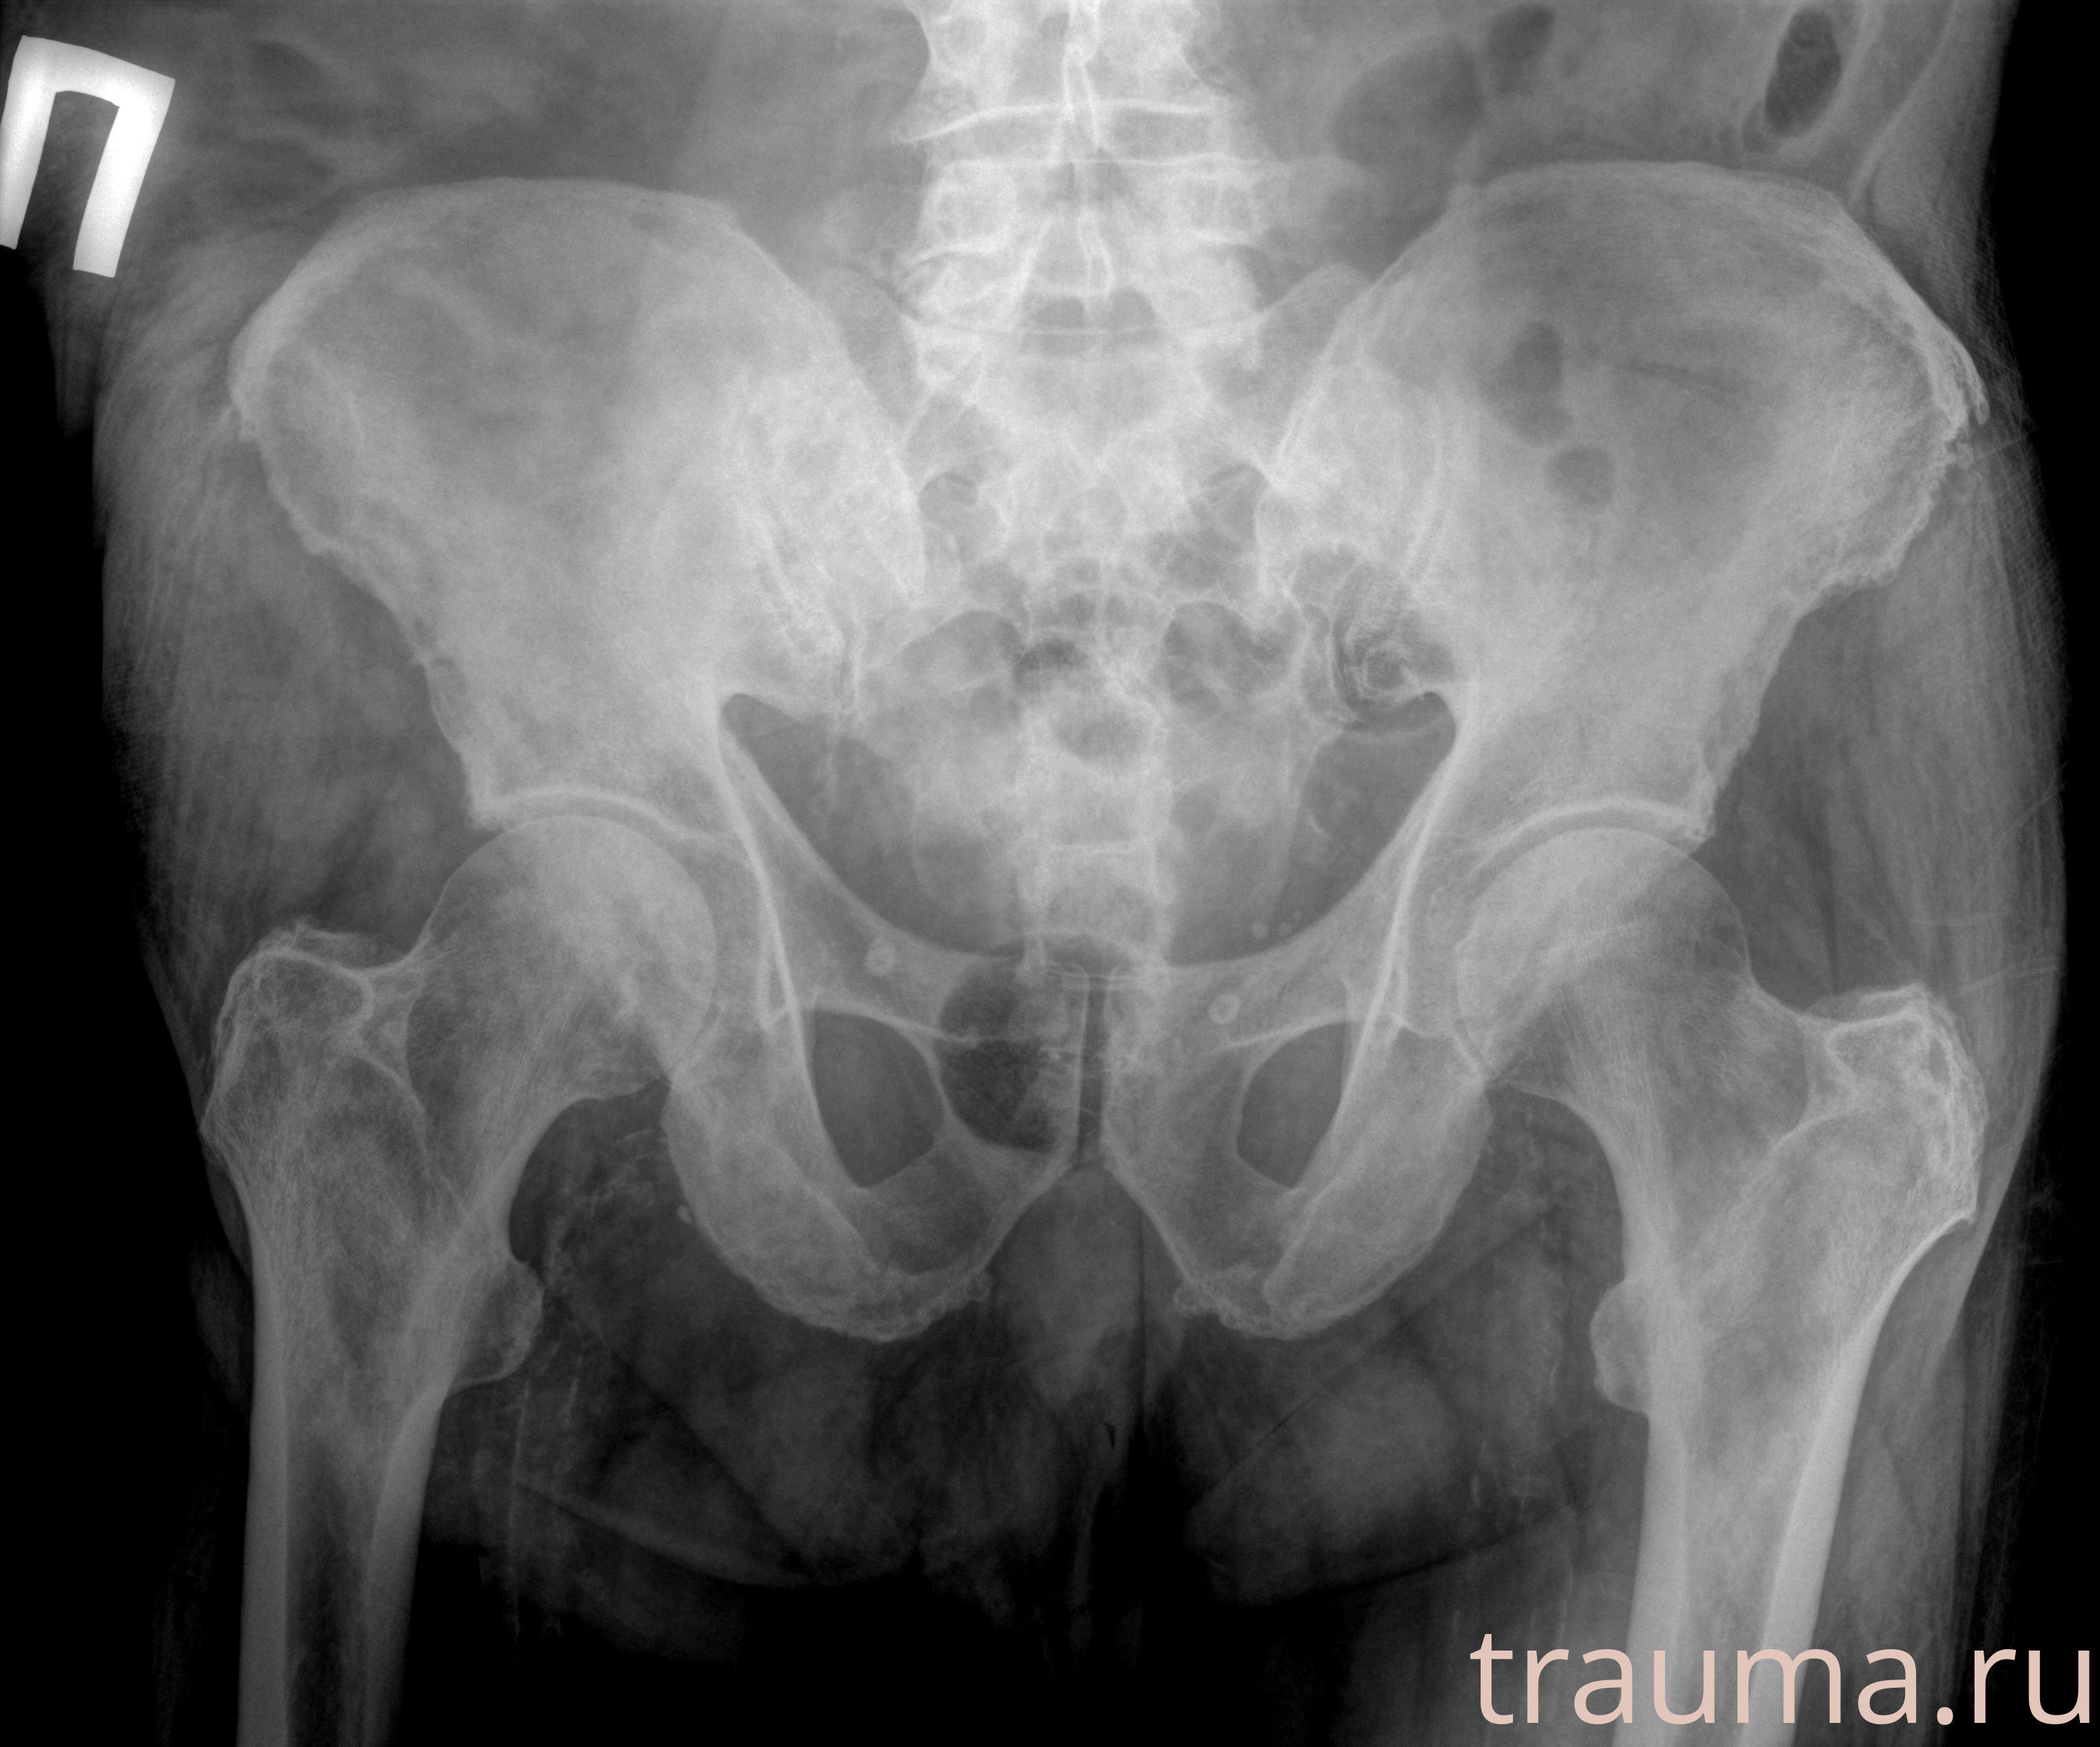

Рентген на дому: по вашему адресу приезжает врач-рентгенолог, травматолог-ортопед с мобильным рентгеновским аппаратом, проводит диагностику травмы или заболевания, делает необходимые рентгенограммы, дает рекомендации по дальнейшему лечению. Получить качественные снимки в домашних условиях возможно благодаря уникальной методике, разработанной МосРентген Центром для института  Склифосовского